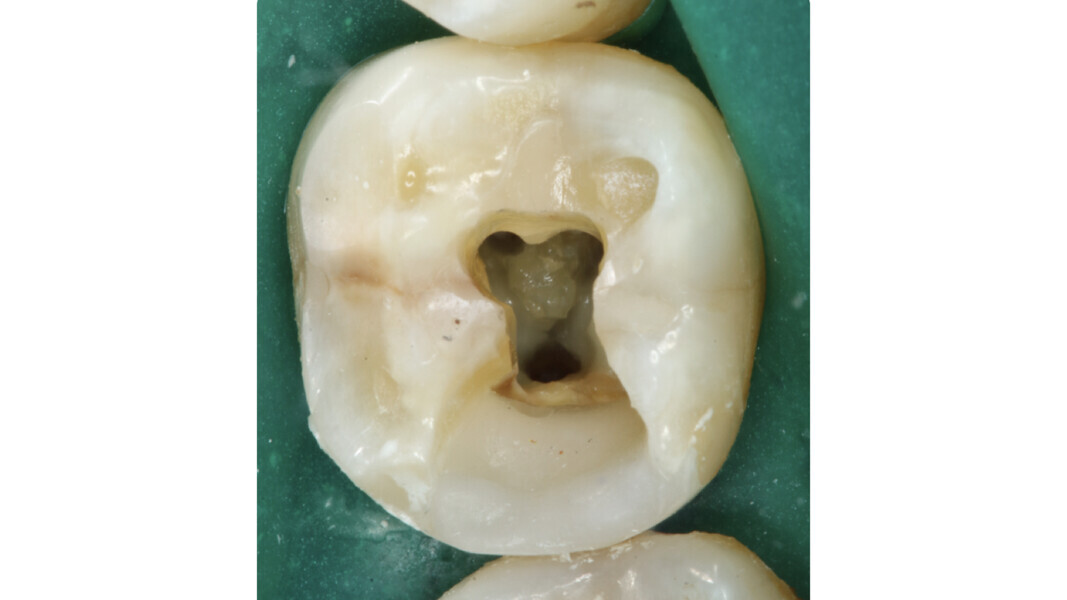

La première étape est stratégique et préparatoire à la réalisation des étapes suivantes. Tout d’abord, la forme doit permettre une visibilité totale du plancher de la cavité pulpaire et des orifices canalaires. L’élimination incomplète du plafond de la cavité pulpaire ou d’une partie du tissu pulpaire (par exemple, les cornes pulpaires) peut compromettre la réussite du traitement.

- Loi du changement de couleur : la couleur du plancher de la cavité pulpaire est toujours plus sombre que celle des parois qui lui sont adjacentes.

La loi du changement de couleur peut être utile lors de l’approche des canaux calcifiés, puisque le praticien peut constamment distinguer les parois plus claires de la cavité pulpaire du plancher plus sombre et donc, rechercher les orifices dans cette dernière zone. Cette caractéristique est constante et sert de guide durant l’exploration des dents sclérotiques.